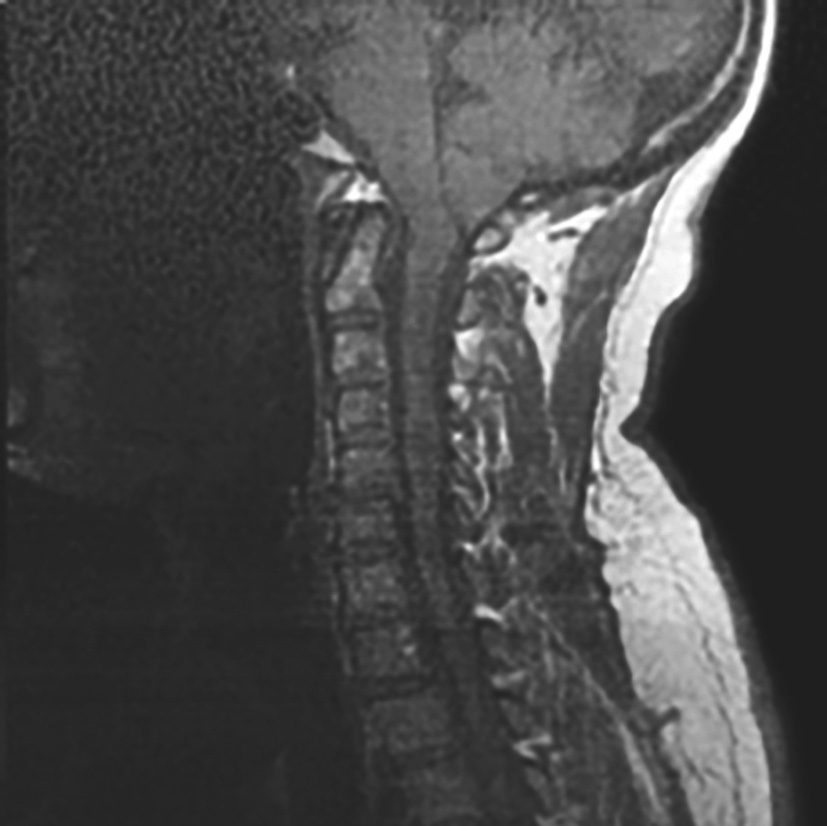

3.辅助检查 头颅CT示枕骨局部缺损,枕部脑膜膨出。头颅MRI示枕部脑膜膨出(图4-1-1)。

图4-1-1 头颅MRI示枕部脑膜膨出

辅助检查:颈椎MRI提示Chiari畸形,合并颈髓空洞(图4-1-2)。

图4-1-2 颈椎MRI